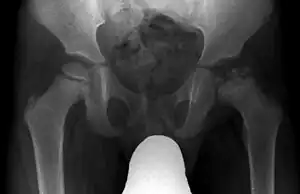

| Radiograph of a person with Legg–Calvé–Perthes disease | |